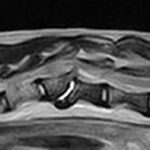

頻繁に嘔吐・下痢をするワンちゃんの精密検査依頼で内視鏡検査のご紹介がありました。内視鏡検査で上部・下部消化管を検査し、粘膜を採取し病理組織検査に出しました。結果は「胃:らせん菌感染を伴う慢性胃炎(中程度)/結腸:慢性腸炎(軽度)」とのことでした。その後かかりつけの先生のところ […]